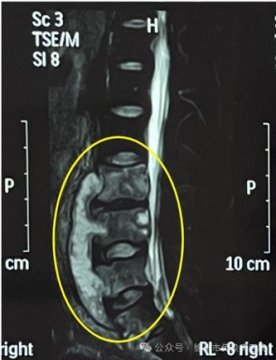

长期腰痛腿痛警惕骨结核

肺结核是人们熟悉的一种传染病,结核菌还可以在人体其他部位感染而发病。比如骨结核是骨或关节感染结核而引起的破坏性病变。发病部位多数在负重大、容易发生劳损的胸椎、腰椎...